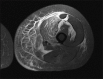

We present five patients with vibrio necrotising fasciitis, a lethal and disabling disease. Two of these patients had a history of exposure to either warm seawater or raw/live seafood, three had underlying chronic liver disease, and four presented with hypotension and fever. There were three deaths and four patients required intensive care unit stays. Among the two survivors, one had high morbidity. Only one patient met the criteria of Laboratory Risk Indicator for Necrotising Fasciitis score > 6. A clinician should suspect possible vibrio necrotising fasciitis if the following are present: contact with fresh seafood/warm seawater, a known history of chronic liver disease and pain that is out of proportion to cutaneous signs. All patients must be managed via intensive care in high dependency units. We recommend a two-step surgical protocol for patient management involving an initial local debridement, followed by a second-stage radical debridement and skin grafting.